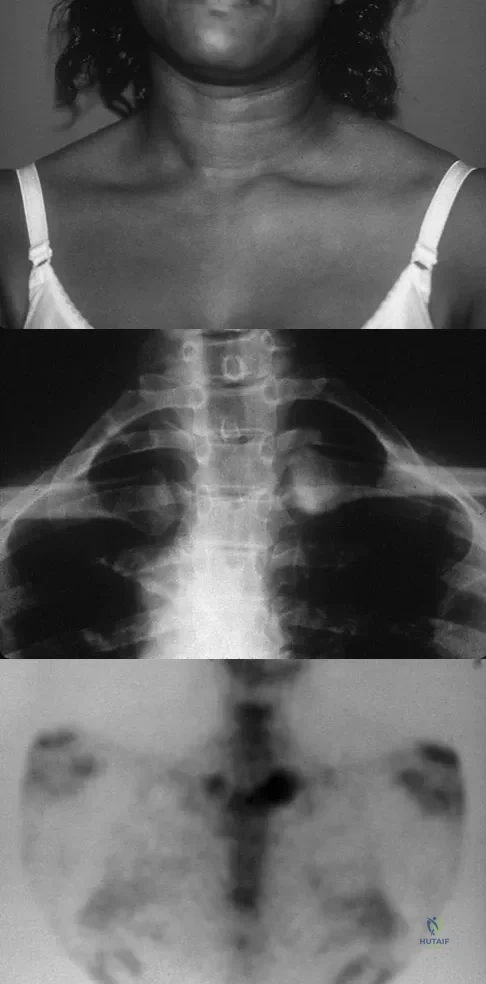

Figure 15a shows the radiograph of a patient who has a chondrosarcoma of the acetabulum. Bone scans are shown in Figures 15b and 15c. Numerous soft subcutaneous masses are present. A clinical photograph of the hand is shown in Figure 15d. What is the most likely diagnosis?

Explanation